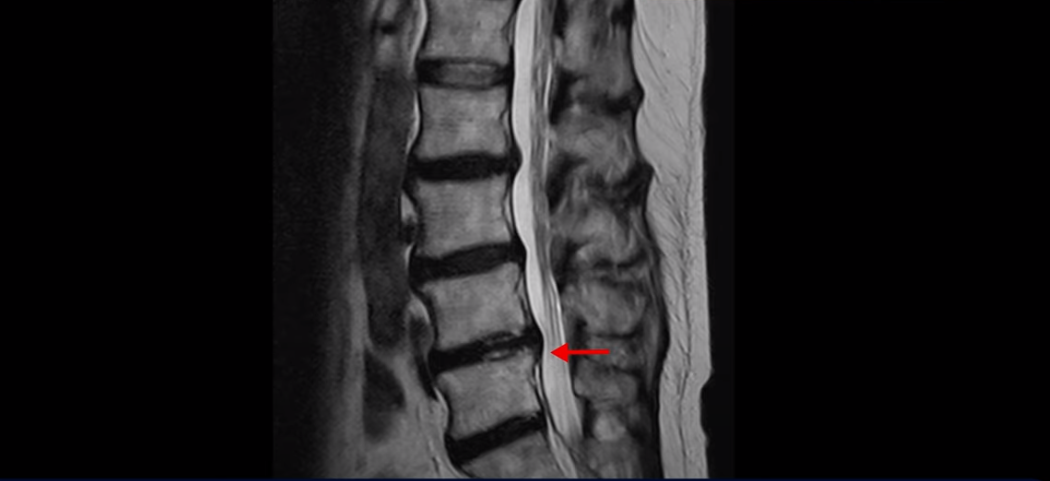

이분 MRI를 보면서 설명 드린 후 어떻게 이렇게 걷지도 못해 휠체어 타시는 환자분이 비수술 치료로 단 몇 주 만에 좋아져서 잘 걷게 될 수 있는지 또 치료는 어떻게 하는지 자세히 설명드리겠습니다.

이분 MRI를 보면 여러 마디가 퇴행이 진행되어 있고

3번 4번과 4번 5번에 중심성 협착이 있는데

4번 5번이 더 심합니다.

또 4번 5번 마디에 오른쪽으로 찢어져서 밀려나온 디스크 탈출이 보입니다.

밀려나온 수핵이 조금 흘러내려 있습니다.